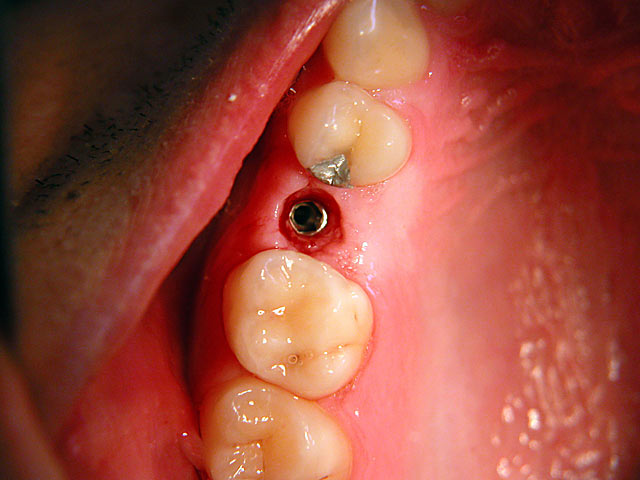

Sofort-Implantation: